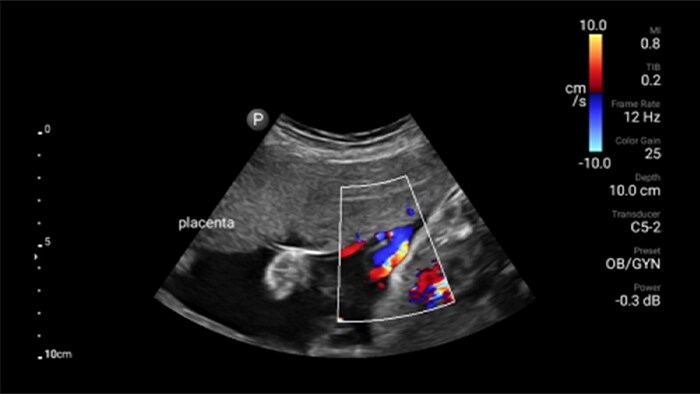

• 5 to 2 MHz extended operating frequency range • 50mm radius of curvature • 2D, color Doppler, M-mode, advanced XRES and multivariate harmonic imaging, SonoCT • High-resolution imaging for deeper applications: abdominal, gall bladder, OB/GYN and lung imaging preset optimizations